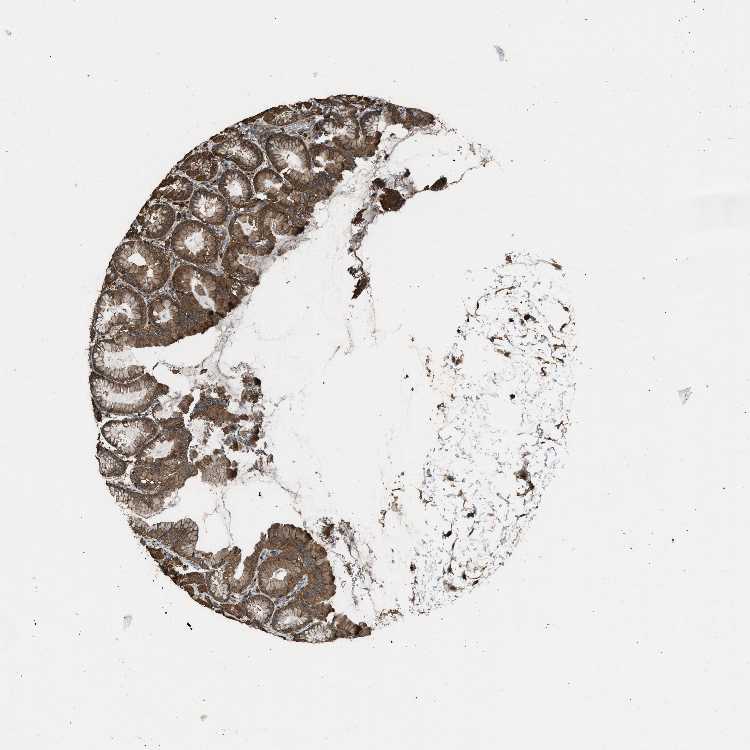

TISSUE PRIMARY DATA STOMACH Show tissue menu

STOMACH 1 - Antibody stainingi

Antibody staining in the annotated cell types in the current human tissue is reported as not detected, low, medium, or high, based on conventional immunohistochemistry profiling in selected tissues. This score is based on the combination of the staining intensity and fraction of stained cells.

Each image is clickable and will lead to virtual microscopy that enables deeper exploration of all samples and also displays staining intensity scores, fraction scores and subcellular localization as well as patient and tissue information for each sample.

Antibody HPA017962Antibody CAB005120

Glandular cells HighHigh